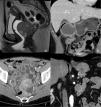

Selected abdominal and pelvic magnetic resonance imaging (MRI) and computed tomography (CT) scan views showing different GIST locations. a) Sagittal T2-weighted MRI scan, showing homogeneous exophytic lesion of intermediate intensity dependent on the anterior wall of the inferior rectum. b) Abdominal CT coronal view in the venous phase, showing a heterogeneous endophytic lesion of the gastric antrum, with a necrotic center, protruding into the pylorus and first part of the duodenum. c) Pelvic CT axial view in the venous phase, showing a heterogeneous exophytic lesion with necrotic/cystic areas dependent on the wall of the ileum. d) Abdominal CT scan in the arterial phase, showing a homogeneous exophytic lesion in the fourth part of the duodenum.

Original figure based on CT and MRI images of GIST tumors carried out at our center.